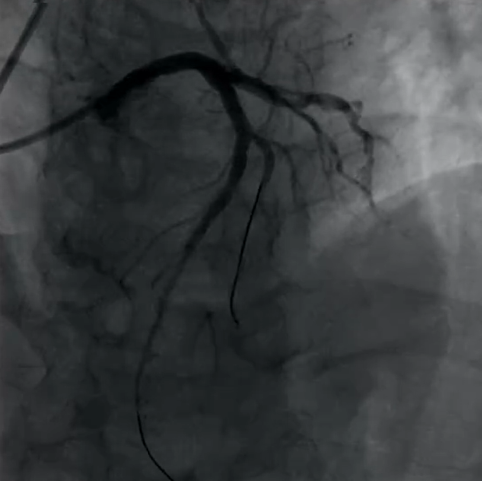

Case 2:前降支对角支分叉处病变,表现为次全闭塞,前降支和对角支明显血流受限,首先使用DCB处理对角支病变,显示血流显著改善,而后主支植入DES并进行充分后扩张,再扩张支架网孔,处理后多个体位造影显示分叉部位治疗效果理想,完美体现了DCB+DES治疗策略的有效性,在降低再狭窄风险的同时保障分支血管的血流。

(Case 2术后)